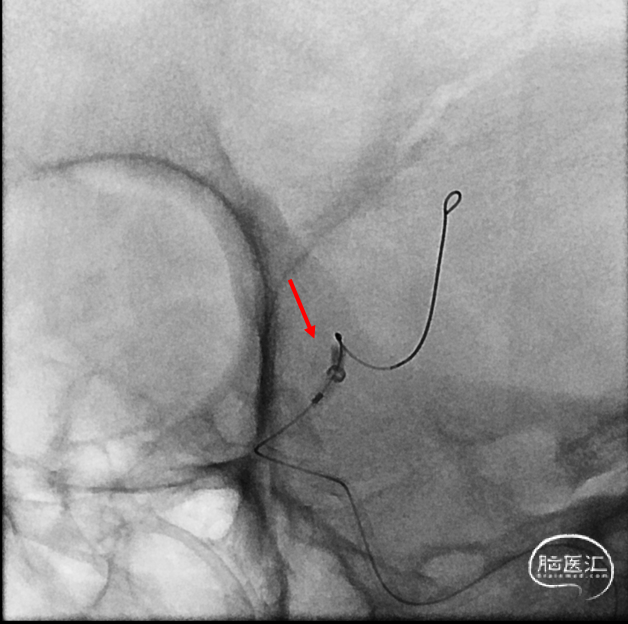

支架重新打开良好

回撤微导管造影

Maverick 2mm/15mm,6atm

L ICA

Post-OP